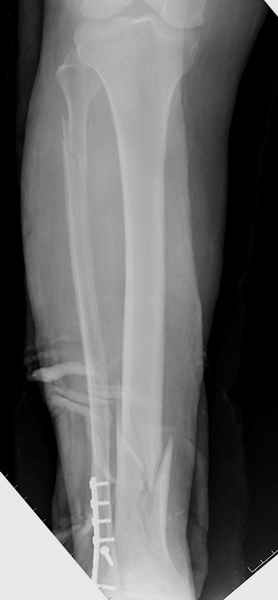

У меня молодой врач на линии, снимки отправил через эл. почту,

спрашивает что делать с больным который поступил недавно, фермер 55 лет падение при пьяной драке в баре, года два назад перенес операцию на лодыжке, на снимках и КТ перелом без вовлечения сустава,

какие будут рекомендации?Djoldas Kuldjanov, MDDepartment of Orthopedic SurgerySt. Louis University Medical Center